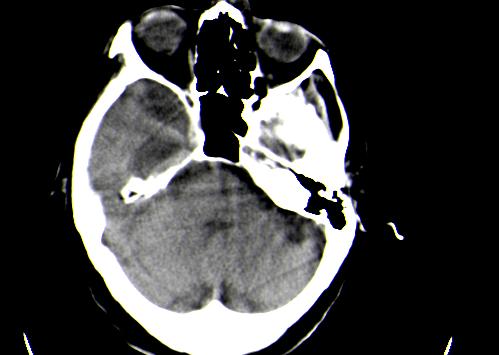

定位:右侧脑室三角区扩大,呈球形,侧脑室颞角扩大,右侧脑室内占位:

定位:右侧脑室三角区扩大,呈球形,侧脑室颞角扩大。

考虑:1、右侧侧脑室三角区室管膜囊肿。

2、脑萎缩。

神经上皮囊肿为先天性疾病,可发生在脉络丛、脑室内、脉络膜裂,少数位于脑质内,侧脑室三角区最为常见。按发生部位和囊壁的细胞学类型可有不同的命名。位于脉络丛者为脉络丛囊肿,常两侧同时发生。脑室内者为室管膜囊肿,多位于侧脑室三角区。脉络膜裂囊肿可以是神经上皮囊肿,也可以是蛛网膜囊肿。 囊肿呈脑脊液样低密度,边界清楚整齐。患者多无症状,有症状者多为头痛、癫痫发作。囊壁很薄,ct一般不能显示,囊壁无钙化。囊肿可有占位效应,表现为相应部位的脑室或脉络膜裂较对侧扩大,脑实质受压,一般不引起脑水肿。增强:囊肿及囊壁均无强化。